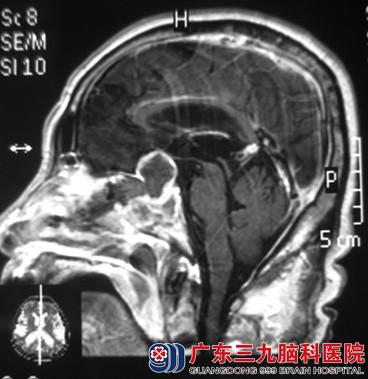

综合神经外科 鲁明主任考虑患者高龄,合并心脏病,术式为经鼻蝶入路。完善相关检查后,由鲁明主任主刀,在全麻下行经鼻蝶鞍区肿瘤切除术,术前导航定位,术中再次导航定位肿瘤位置,显微镜下见灰白色肿瘤组织,呈胶状,全切肿瘤,手术顺利结束。术后患者经脑专科治疗和护理,未出现尿崩、离子紊乱、脑脊液漏等手术并发症,自诉视力、头晕症状较前好转。术后病理结果为:“鞍区”垂体促性腺激素腺瘤。

术后